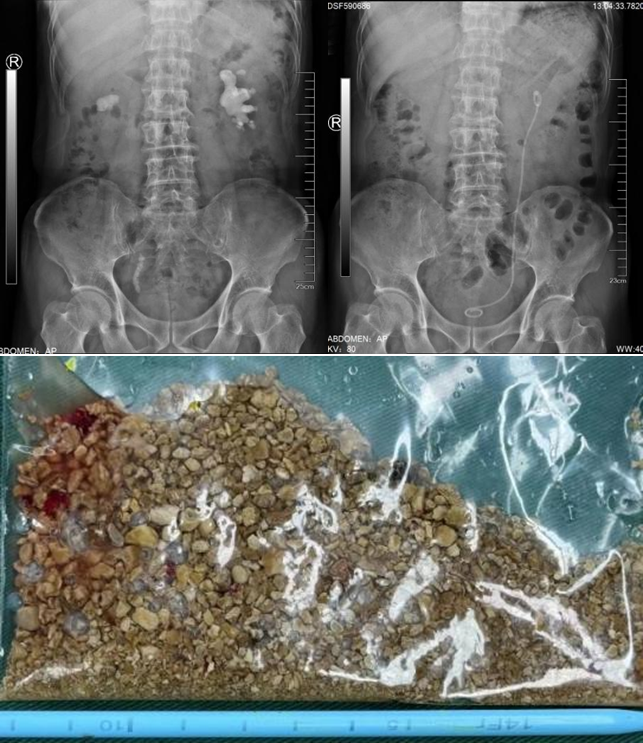

患者在外院检查发现:CT提示右肾多发结石,右侧肾盂及输尿管扩张积水。患者既往曾多次行输尿管镜手术,存在右输尿管狭窄病史。患者入院后浦金贤主任组织科室讨论指出,患者右肾下盏多发结石,且部分位于下盏小盏,角度刁钻,手术难度大,单一经皮肾镜或输尿管软镜难以完全清除结石。周守军主任带领结石团队全力准备手术,采取斜仰卧位经皮肾镜-输尿管软镜(PCNL-RIRS)双镜联合的手术方式,一期手术彻底清除结石,复查结石无残留,达成理想的治疗效果。

该例患者2年来出现右腰部反复疼痛,伴尿频尿急尿痛、肉眼血尿。来我院前曾经在外院检查B超提示右肾结石,选择进行保守治疗并定期复查。近期患者再发右腰部疼痛来我院就诊,B超检查提示:右肾结石,右肾囊肿。尿常规检查提示:白细胞:1332个/ul,予以口服抗生素治疗1周后收住入院。入院后进一步完善相关检查,CT检查提示:右肾结石,大小约3.1x1.8cm,右肾囊肿大小约5.0x3.5cm,复查尿常规:白细胞:191个/ul。浦金贤主任带领科室成员仔细阅片后指出,患者结石位于肾盂输尿管连接处,负荷较大,且尿常规检查显示白细胞较高,考虑结石伴发感染可能性大,需严格控制感染,术中应注意肾盂内压力,减少术后严重感染风险。同时,患者右肾囊肿体积较大,可以考虑同次手术一并处理。根据患者病情特点,周守军主任采用腹腔镜微创手术的方式,一期手术同时行腹腔镜肾盂切开取石和腹腔镜肾囊肿去顶术,将结石完整取出、肾囊肿去顶减压,一次手术解决两个问题。患者术后迅速康复,未出现发热、尿瘘等并发症,顺利出院。